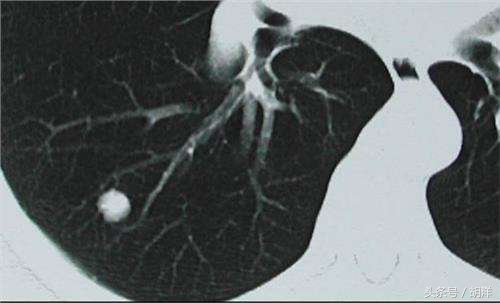

肺部小结节

肺部小结节现在几乎成了40岁以上人群体检所发现问题的“新常态”,之所以越来越受到医生和患者的重视,是因为其中一部分结节是早期肺癌的表现。然而就目前的科技手段,1cm以下的结节几乎无法通过内科方法明确性质,大部分需要通过长期随访复查CT来观察结节变化,一旦结节快速增大,呈现出恶性表现时,立即考虑手术根治。这里就牵涉到复查间隔的问题,大家知道CT在观察小结节中的作用是不可替代的,但它又有一定的辐射,最好是既能观察结节又尽可能的减少次数,这时候对吸烟者和不吸烟者就会有一个区别对待,不吸烟的人群复查时间的间隔更长,停止复查所需的时间更短。